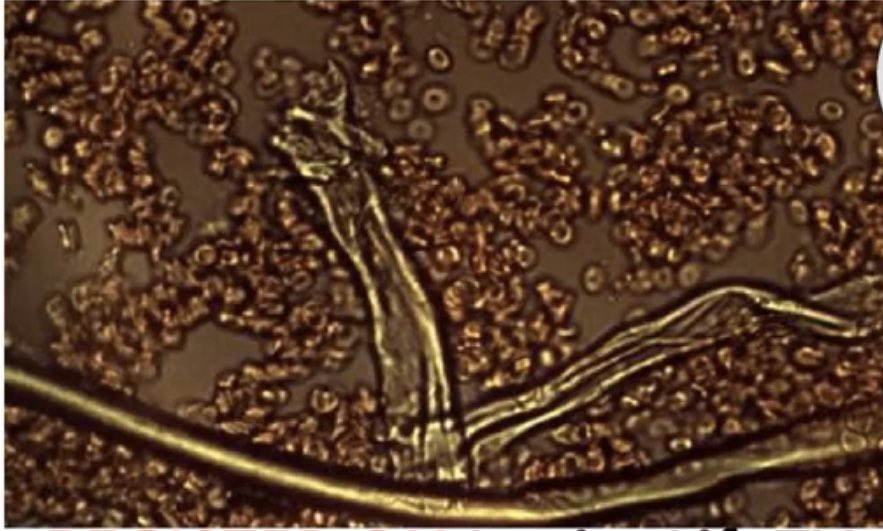

BREAKING: THE JABBED ARE GROWING 3-D STRUCTURES - IN THEIR SKIN...ALMOST 4 YEARS AFTER INJECTION! Big interview coming to the Dr Jane Ruby Show with Pfizer/Moderna incubation study lead investigator, Dr. Youngmi Lee's second round of findings. Follow my work on the bioweapon, fake pandemics, & all medical lies at http://Rumble.com/drjaneruby

@RealDrJaneRuby - DR JANE RUBY™️

This multi part interview with Dr Lee directly from her offices in Seoul will explain these findings and the pictures from her expertise in stereo microscopy. The jab should be very angry, this is mass assault and mass genocide

THE JABBED "ARE [BIOWEAPON] RESEVOIRS" Contrary to what the chorus of highly paid Frontline doctors is now telling you, the jabbed are NOT OK after one or two years. The Pfizer/Moderna incubation study conducted in Korea by Dr. Youngmi Lee resulted in self assembling three dimensional foreign objects in the blood and semen of the jabbed...TWO YEARS post injection. We must start focusing on how to reverse/remove the products of these injections! Follow my work on all the bio weapons at rumble.com/drjaneruby

This is semen from a "healthy" 38 year old male, who took 3 Pfizer C19 shots TWO YEARS ago. This was incubated in normal saline (0.09%) and self assembled many of these 3-D ribbon structures in just 30 days! The man reported no post injection side effects. Why is no one outraged ?